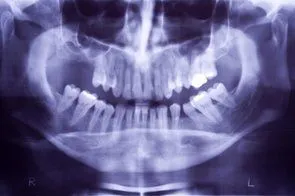

iStock_000002879017XSmall.jpg Loss of posterior teeth may result in excessive forcesbeing placed on your remaining teeth.  Fortunately, the use of dental implants and crowns allow you to replace these missing teeth.  However, the position of the sinus in the upper posterior areas may be too low for proper placement of dental implants.

A simple procedure allows the sinus floor to be repositioned, creating enough space to properly place an implant.  Various grafting materials are used to encourage your bone to grow more quickly into the area, helping to stabilize the dental implant. Replace with your own bone in this area the grafting material as it grows into the area.

Under certain conditions, an even simpler procedure can be utilized.  When possible, the bone remaining under the sinus floor is gently “pushed up”, thus lifting the floor of the “dropped” sinus.  Bone replacement materials are then placed beneath this lifted bone.  Once again the bone materials are replaced as your body grow new bone into this area.